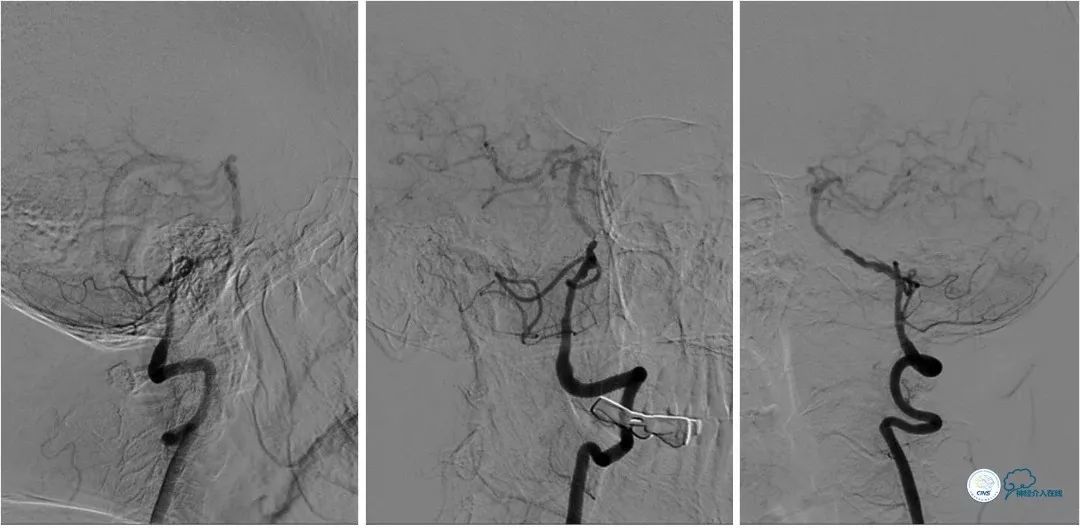

撤出球囊导管,送入wingspan (2.5mm x 15mm )自膨式支架,造影提示支架释放后支架贴壁良好,前向血流TICI 3级。右椎动脉V4段经返流显影,但病变受支架影响显示狭窄程度加重(图10)。

图10

术后复查头颅CTA:基底动脉支架内通畅(图12)。

图12